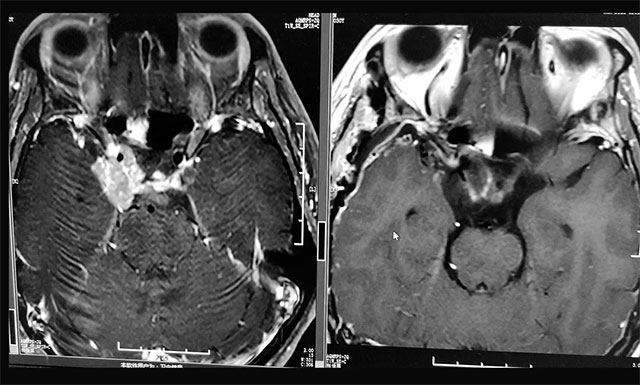

▲ 术后影像显示残余肿瘤被切除

在充分准备并征得家属同意后,李士其教授在吴治群博士、黄秀夫医生协助下为患者行开颅手术,经翼点入路将残余约2.5cm*2cm*2cm大小肿瘤切除。

术后第二天,患者视力已有明显改观,并能正常沟通交流,目前正在康复中,同时李士其教授叮嘱患者出院后要注意定期复查。